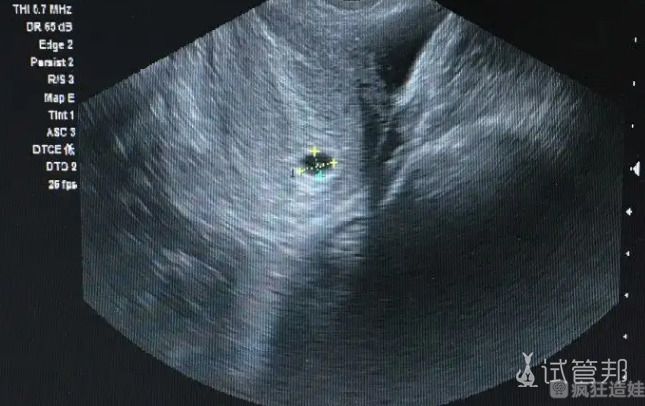

因为我卵巢早衰,所以一直不能自然怀孕。然后就踏上了去新加坡莱佛士医院做二代试管婴儿的路途。整个促排卵和胚胎培养过程都是比较顺利的。所以我非常高兴。然后就是胚胎移植。我胚胎移植了2枚,一个男胚,一个女胚。剩下的胚胎就冷冻储存起来。其实就是为了预防没有一次胚胎移植成功,还有其他胚胎可以用。

那七天是我备孕这些年觉得最放松的一次。我就抱着顺其自然的心态,反而我老公比我还紧张,整天担心我。好在一切顺利,后面去医院做检查,已经安全着床啦,还是龙凤胎。成功那一刻,我真的眼泪止都止不住。那一刻我非常感谢自己。说实话,我当初也担心会不成功,但总归还是要试一把,才知道到底是不是对的。反正我希望大家能坚持下来,想要一个宝宝,真不难。但是我一次就能成功怀上龙凤胎真的非常幸运。